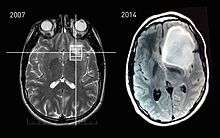

MRI scans of an astrocytoma patient, showing tumor progression over the course of seven years.